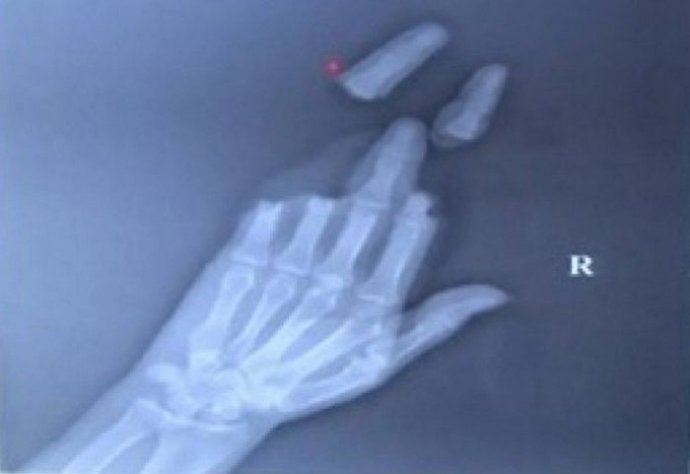

결국 연을 들고 있던 남성은 손가락 3개가 절단됐고 도와주던 친구도 손가락 신경이 손상되는 부상을 입게 됐다.

엑스레이 촬영을 한 50대 남성은 그야말로 끔찍했다. 손가락이 모두 절단돼 봉합 수술을 받았고 도와주던 친구도 손을 수십바늘 꿰매는 수술을 받게 됐다.